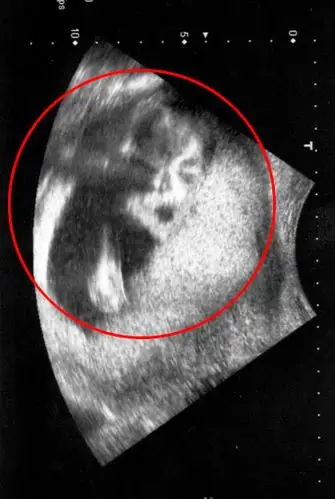

医院b超显示蒋女士已怀孕